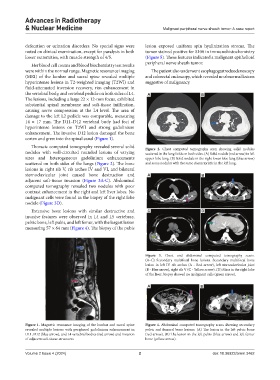

Thoracic computed tomography revealed several solid Figure 2. Chest computed tomography scan showing solid nodules

nodules with well-circuited rounded lesions of varying scattered in the lung fields on both sides. (A) Solid nodule (red arrow) in left

sizes and heterogeneous gadolinium enhancements upper lobe lung. (B) Solid nodule in the right lower lobe lung (blue arrow)

scattered on both sides of the lungs (Figure 2). The bone and some nodules with the same characteristic in the left lung.